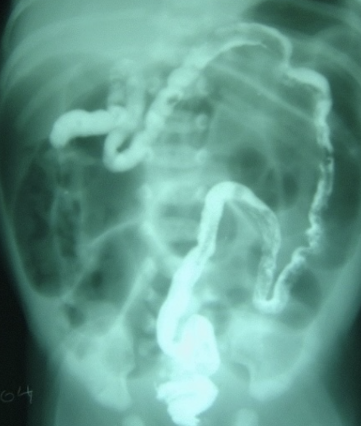

Contrast enema shows an empty microcolon in case of _____

_____ appearance is the characteristic finding seen in Barium enema X-ray in a case of intussusception.